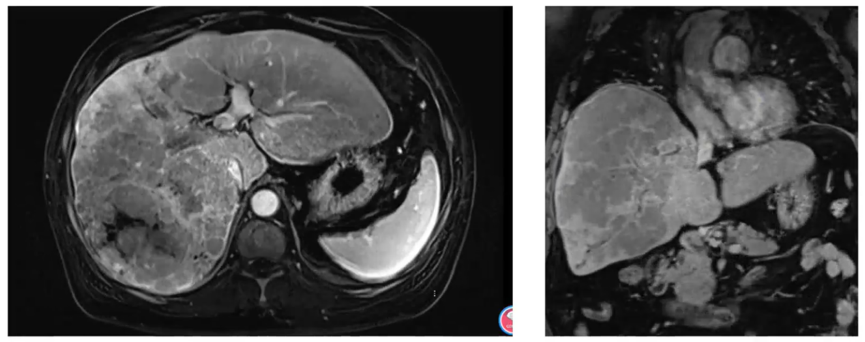

影像资料:2021年8月26日MR示,巨块型肝细胞癌伴多发肝内转移;门静脉右支主干及分支广泛癌栓,累及至门静脉左支主干;肝右、中静脉受侵(图1)。

图1. 2021年8月26日MR